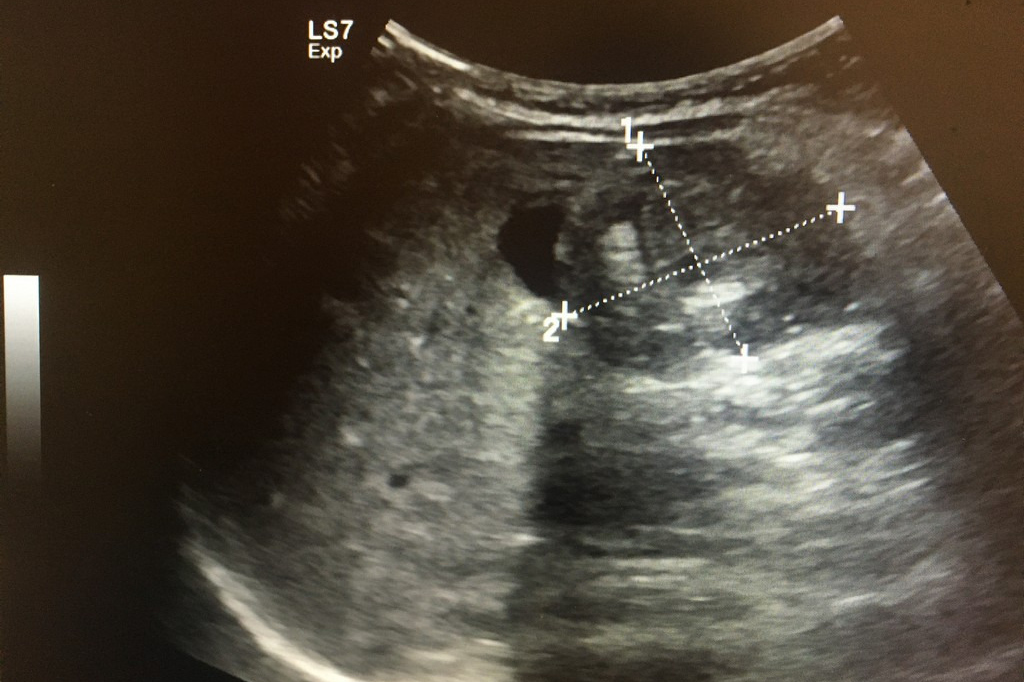

초기 증상이 애매하고 흔한 소화기 증상과 유사하기 때문에 크론병은 진단이 늦어지는 경우가 많습니다. 그러나 진단이 지연될수록 염증이 깊어지고 장 손상이 누적되어 수술적 치료가 필요한 상황으로 이어질 가능성이 높아집니다. 따라서 증상이 반복되거나 장기간 지속된다면 단순 증상 완화에만 의존하지 말고 전문적인 평가를 받는 것이 필요합니다.

크론병은 급성으로 끝나는 질환이 아니라, 증상이 좋아지는 관해기와 다시 악화되는 재발기를 반복하는 것이 일반적입니다. 관해기에는 비교적 일상생활이 가능하지만, 재발기에는 증상이 급격히 악화되어 입원 치료가 필요한 경우도 적지 않습니다. 또한 질환 기간이 길어질수록 장 협착이나 누공 같은 합병증 위험이 증가하기 때문에 조기 진단과 지속적인 관리가 매우 중요합니다.